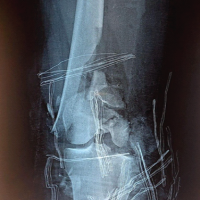

A 38-year-old male with a history of right shoulder instability in the past was managed with the Latarjet procedure 4 years ago. The patient had an uneventful post-surgical period, but symptoms recurred a year later without any significant event. He presented to us with complaints of right shoulder pain and instability since 3 years, having experienced multiple episodes of dislocations, which were managed with closed reduction at different centers. On examination, the Beighton score was five. 1 cm wasting was noted in the right arm. Sensations over the arm were intact. Tests for anterior instability, such as apprehension, relocation-release, and anterior drawer, were positive. There were no signs of instability in posterior and inferior directions. He had a nearly complete range of motion in all planes but was apprehensive to use the arm for overhead activities and lifting heavy objects. X-ray and computed tomography (CT) scan were done, which revealed a displaced as well as a broken screw near the right glenoid, likely from the previous surgery (Fig. 1 and 2). The anteroinferior part of the glenoid appeared to be resorbed. Bone loss was quantified using the perfect circle method in oblique sagittal plane, which was approximately 27% (Fig. 3). Infective etiology was ruled out via clinical examination and radiological investigations.

Figure 2: Computed tomography scan showing resorbed glenoid bone and a displaced screw marked with a white arrow.